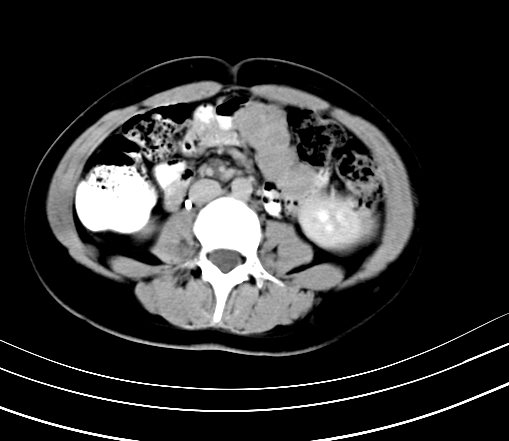

动脉期

静脉期

延时5分钟

延时10分钟